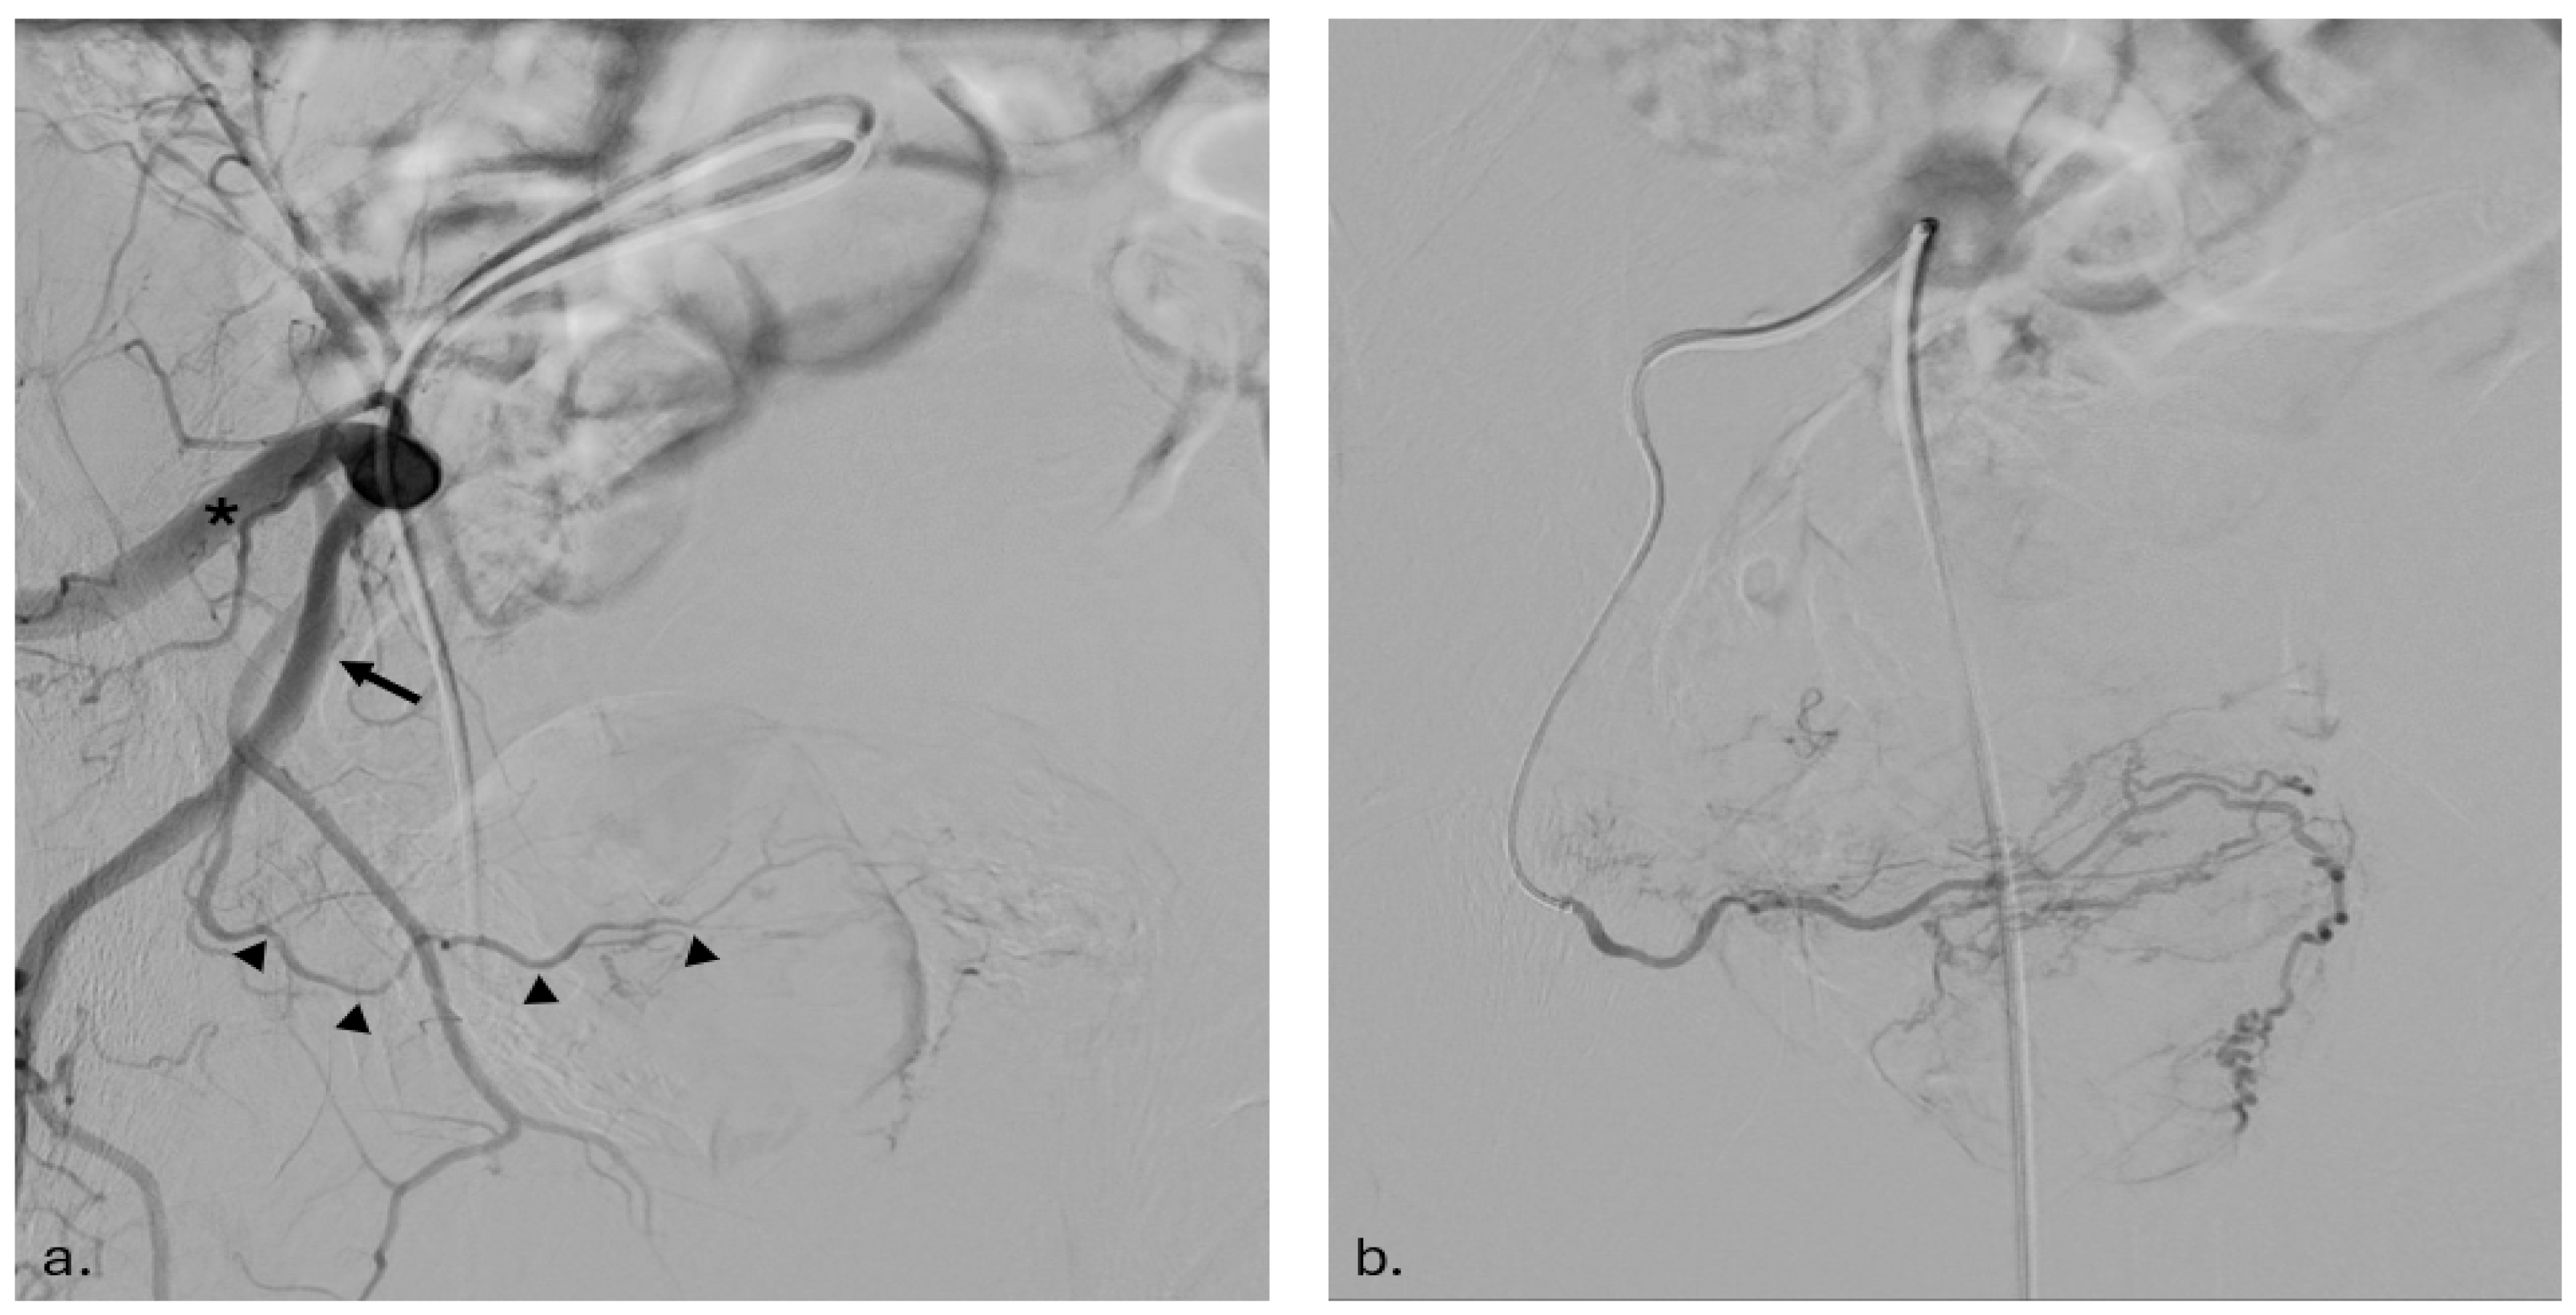

2.3.1. Arterial Access and Imaging

2.3.2. Catheterization and Embolization

2.3.3. Post-Procedure Imaging and Verification